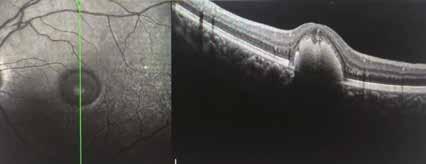

12 MESI DHA ALGALE (OMEGAL DHA) Visus 9-10/10;0.04 logm.+0.75 sf

Fig. 1. Imaging infrarosso ed OCT mostra un Rapido ed insolito appianamento di ampio distacco dell’EPR maculare in DMS in donna di 75 aa, con significativo miglioramento visivo da 0.6 logmar a 0.1 logmar e nell’integrità delle linee recettoriale nella zona ellissoide, in particolare in assenza di aree atrofiche successive al riassorbimento.

Baseline: notare chiazze biancastre segno di sofferenza EPR

18 mos dopo formula areds2 & DHA Algale: chiazze tondeggianti scomparse

9 mos dopo rimozione DHA algale dalla formula Areds2

Fig. 2. Notare che nei 18 mesi di integrazione l’auto-fluorescenza della macula della paziente di 78 aa con AMD rimane libera da significative aree atrofiche, fintanto che il paziente continua ad assumere la formula antiox AREDS2 arricchita di olio algale, mentre solo 9 mesi dopo la sostituzione del DHA algale con DHA da pesce Krill, si osserva la rapida comparsa di significative ed invalidanti aree atrofiche a coinvolgere diffusamente l‘area maculare,altamente impattanti sull’acuità visiva della paziente fino a rendere estremamente difficoltosa la capacità di lettura, con un calo visivo fino a 2/10 da 8-9/10.